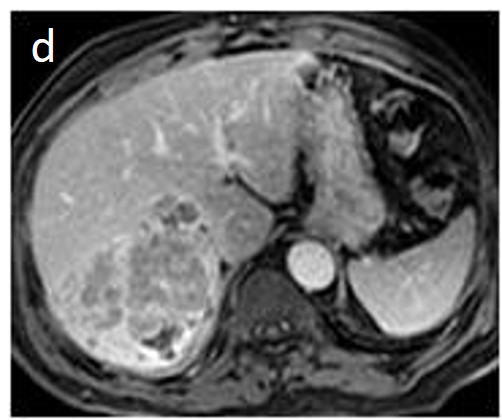

Fatty change is encountered in approximately 40% of early HCCs [143]. With increasing tumor size and histologic grade, fat usually regresses and the percentage drops to 6% in moderately-differentiated HCCs [144], only to increase again in highly de-differentiated tumors. This occurs along with the diminished arterial supply, suggesting a connection between reduced blood flow, hypoxia, and steatogenesis [145]. MRI is superior to CT in detecting fatty change with the use of chemical shift sequences, which show the characteristic signal drop on the opposed-phase compared to the in-phase (Figures 12 and 13). Intratumoral fat can also be used to exclude cholangiocarcinoma, which is also associated with cirrhosis. Nevertheless, the added value of fat identification in a HCC is debatable because, when detected, other more suggestive features (like the vascular pattern) are already present [123].

Figure 13. Sixty-five-year-old man with cirrhosis. On the T2 sequence, a nodular high T2 lesion is vaguely seen (arrowheads) (a). The lesion appears hyperintense on the in-phase image (b) and slightly hypo-intense on the out-of-phase image (arrowheads) (c), suggesting the presence of fat. On the hepatobiliary phase after gadoxetic acid administration, a small nodule with markedly decreased signal (no contrast uptake) is evident in the left aspect of the larger lesion (arrow), suggesting focal de-differentiation in a dysplastic fatty nodule and early HCC formation (“nodule in nodule” sign) (d).